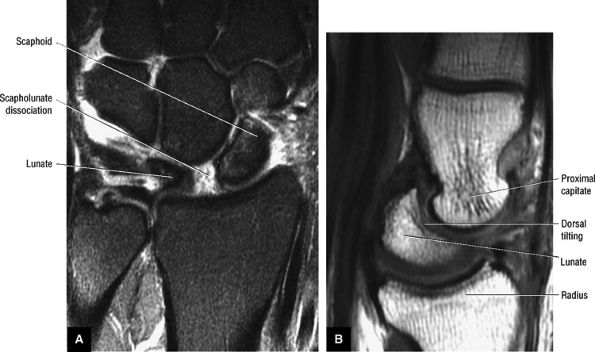

However, a fluid-filled gap interposed between the membranous scapholunate ligament and the cartilage or bones should be interpreted as a perforation or detachment. Such membranous scapholunate ligament perforations and detachments are more common with advancing age (similar to tears of the TFC central disc), and in isolation may not necessarily result in carpal instability or significant symptoms. The volar-most images demonstrate the volar scapholunate ligament, which courses obliquely and attaches to bone on either side of the ligament. Tears of the volar and radial aspects of the scapholunate ligament suspected in the coronal plane can be confirmed in the axial plane. After identifying a scapholunate ligament tear, the scapholunate interval is assessed for widening, reactive bone marrow changes on either side of the scapholunate articulation, and bony or cartilaginous avulsions at the site of tearing or detachment. In addition, in the setting of scapholunate ligament tears, associated patterns of carpal instability, such as dorsal intercalated segment instability (DISI) pattern, can be identified on corresponding sagittal images.

DISI with dorsal tilting of lunate, an increased capito-lunate angle (more than 30°), and an increased scapho-lunate angle (more than 80°) (Fig. 10.98)